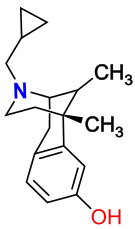

Benzomorphans

- 5,9 alpha-diethyl-2-hydroxybenzomorphan (5,9-DEHB)

- 8-Carboxamidocyclazocine (8-CAC)

- Alazocine

- Anazocine

- Bremazocine

- Butinazocine

- Carbazocine

- Cogazocine

- Cyclazocine

- Dezocine

- Eptazocine

- Etazocine

- Ethylketazocine

- Fedotozine

- Fluorophen

- Gemazocine

- Ibazocine

- Ketazocine

- Metazocine

- Moxazocine

- Pentazocine

- Phenazocine

- Quadazocine

- SKF-10047

Structures

| Benzomorphans | ||||

|---|---|---|---|---|

5,9 alpha-diethyl-2-hydroxybenzomorphan 5,9 alpha-diethyl-2-hydroxybenzomorphan (5,9-DEHB) |

8-Carboxamidocyclazocine 8-Carboxamidocyclazocine |

Alazocine Alazocine |

Anazocine Anazocine |

Bremazocine Bremazocine |

Butinazocine Butinazocine |

Carbazocine Carbazocine |

Cogazocine Cogazocine |

Cyclazocine Cyclazocine |

Dezocine Dezocine |

Eptazocine Eptazocine |

Etazocine Etazocine |

Ethylketocyclazocine Ethylketocyclazocine |

Fedotozine Fedotozine |

Fluorophen Fluorophen |

Gemazocine Gemazocine |

Ibazocine Ibazocine |

Ketazocine Ketazocine |

Metazocine Metazocine |

Moxazocine Moxazocine |

Pentazocine Pentazocine |

Phenazocine Phenazocine |

Quadazocine Quadazocine

|

Thiazocine Thiazocine |

Tonazocine Tonazocine |

Volazocine Volazocine |

Zenazocine Zenazocine |

|||